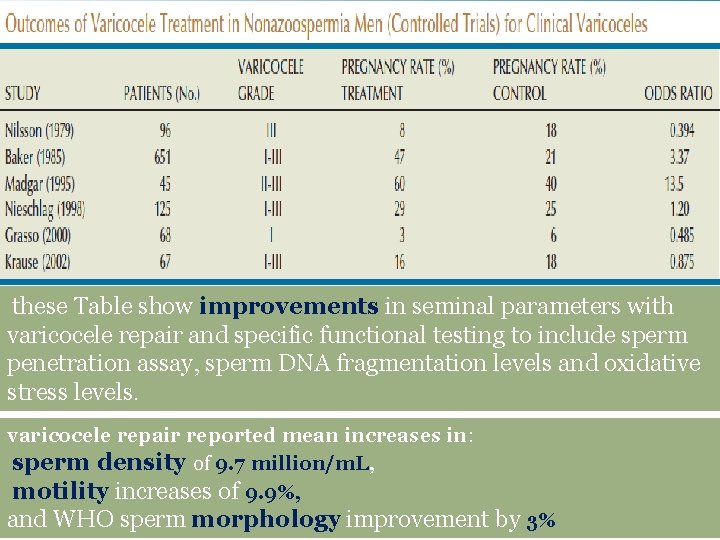

these Table show improvements in seminal parameters with varicocele repair and specific functional testing to include sperm penetration assay, sperm DNA fragmentation levels and oxidative stress levels. varicocele repair reported mean increases in: sperm density of 9. 7 million/m. L, motility increases of 9. 9%, and WHO sperm morphology improvement by 3%